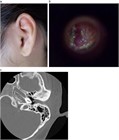

著者: 小川洋 福島県立医科大学会津医療センター 耳鼻咽喉科学講座

1. 慢性の外耳道炎、外耳道湿疹は全身的な皮膚疾患に伴うことがある。乾癬やアトピー性皮膚炎、接触性皮膚炎が原因となっているものに関しては問診、パッチテストが必要となる。

1. 急性限局性外耳道炎と急性乳様突起炎はどちらも外耳道が腫脹し耳介が変位することがあるが、起因菌の頻度が異なること、治療方針が異なることから鑑別が重要となる。

1. 通常急性外耳道炎の場合真菌感染の頻度は10%程度と低いが、これらは通常の治療に抵抗するため、このような場合には真菌感染を強く疑い、真菌に対する治療を行う。